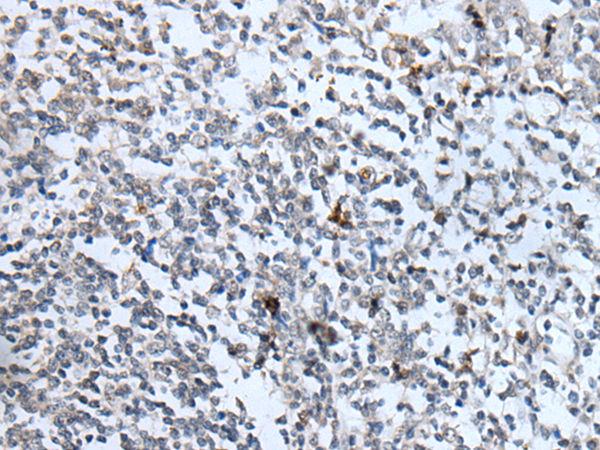

分类: 科研抗体货号: P05928别名: KLR; CD314; NKG2D; NKG2-D; D12S2489E应用: WB,IHC反应种属: Human, Mouse, Rat